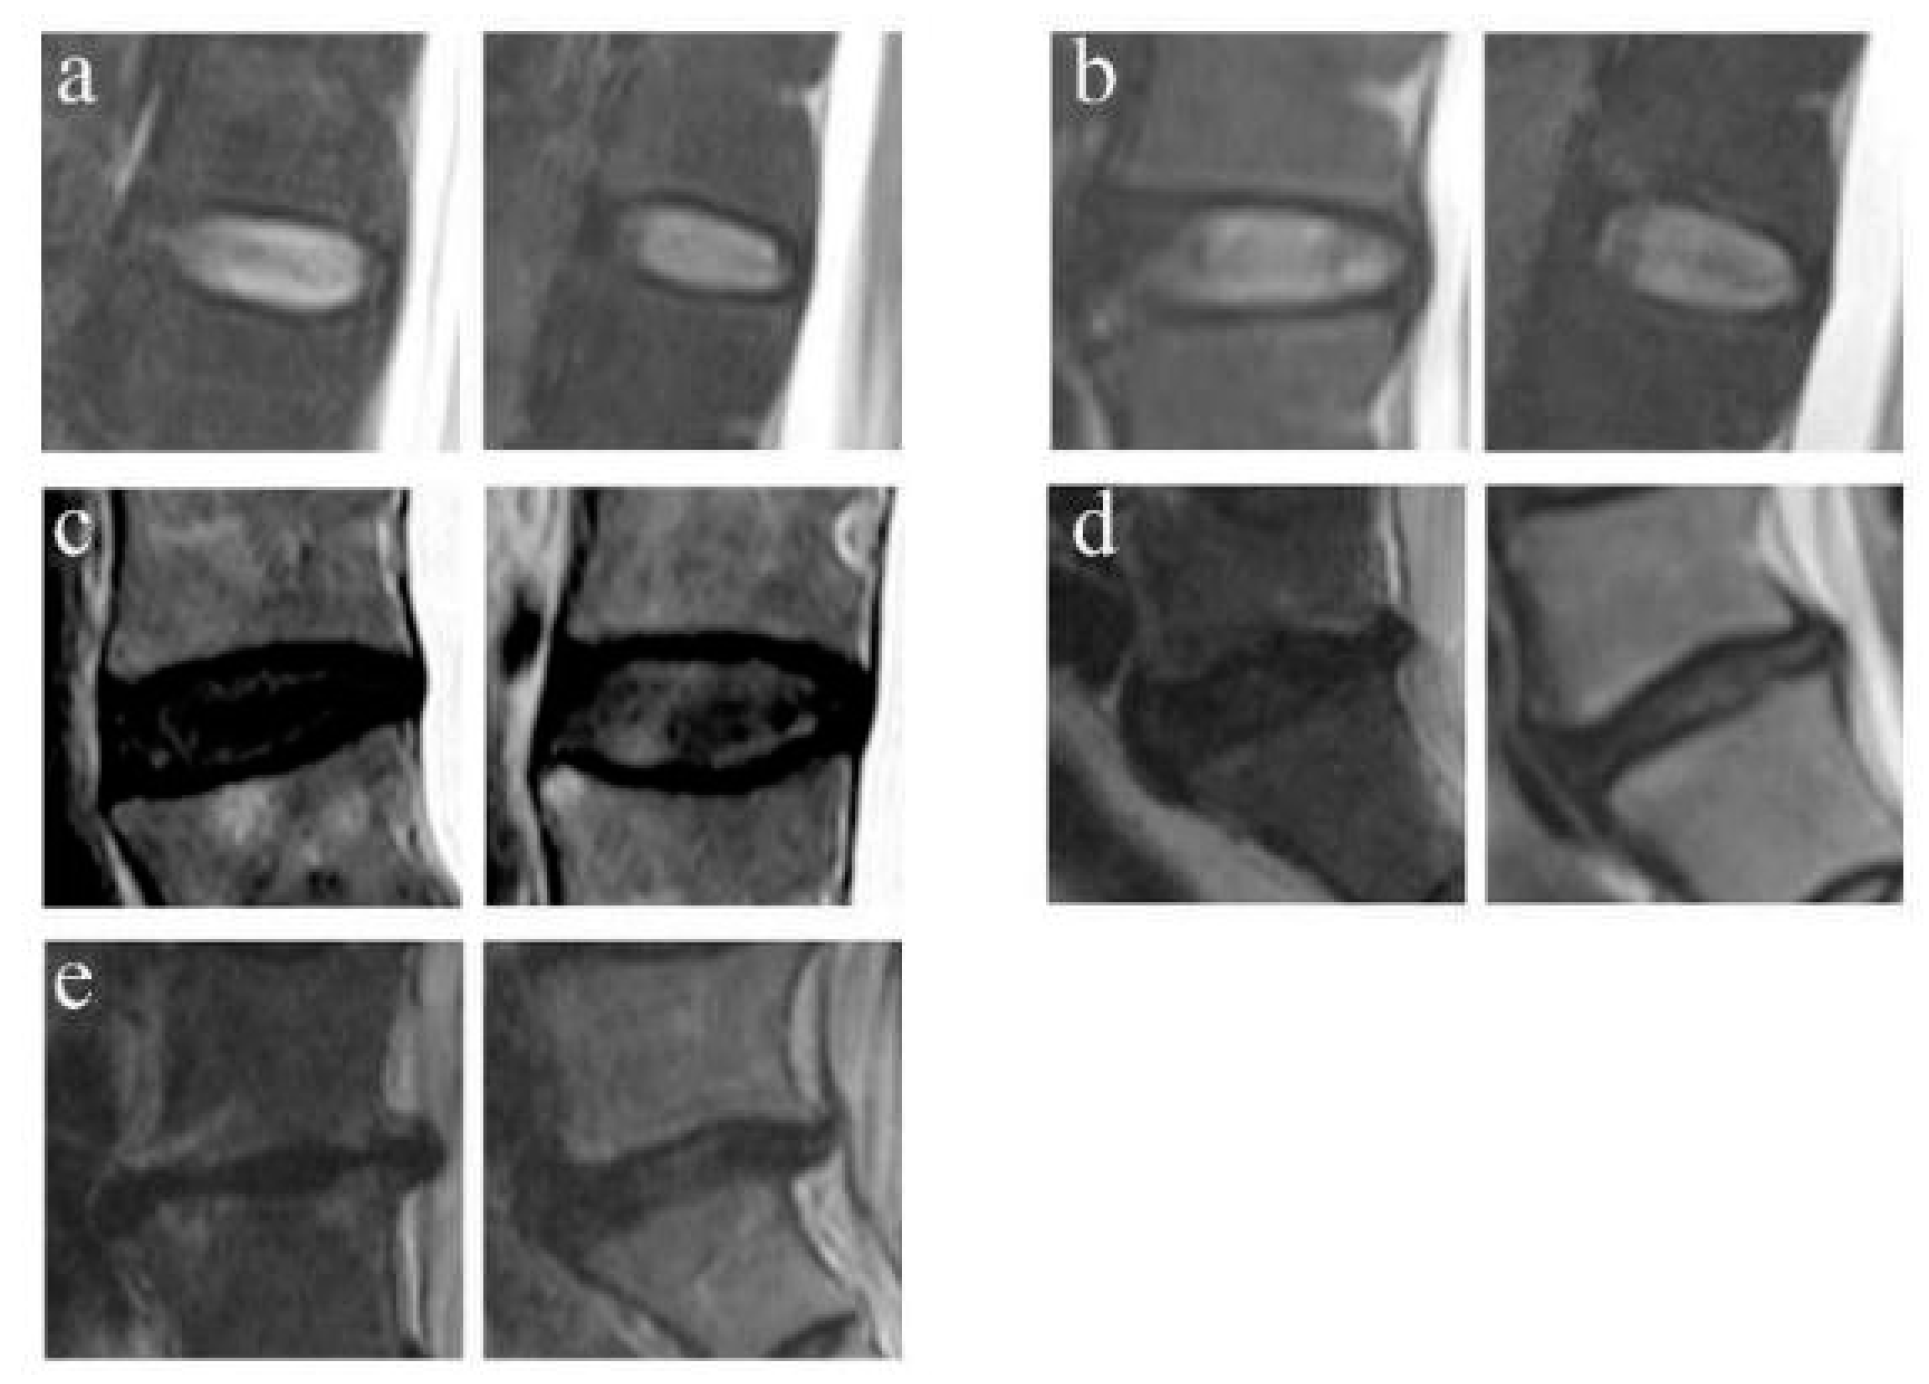

2.4.3. FJOA Grading

The FJOA was classified into 4 grades via the criterion of Pathria et al. [10] on CT. Grade 0 corresponds to a normal facet joint and grade 3 corresponds to a severely degenerated joint (Figure 3).

Figure 3.

Example of FJOA on CT. (a) Grade 0: normal facet joint. (b) Grade 1: mild osteoarthritis facet joint with narrow space and small osteophytes. (c) Grade 2: moderate osteoarthritis with sclerosis or subchondral erosions. (d) Grade 3: severe osteoarthritis with marked osteophyte.